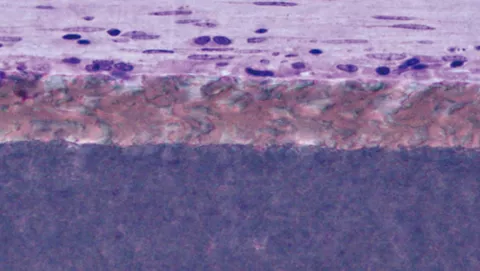

ウサギの上顎部位に4 ヶ月埋植したメンブレンの様子。骨とメンブレンの境界部において、新生骨(紫)がメンブレン(青)と直接接触していることがわかる。

骨とメンブレン境界部の高倍率画像。骨組織とメンブレンが直接接している境界面において、メンブレン内にミネラル(黒い斑点)が沈着していることを示している。

骨とメンブレン境界面における元素分析画像。カルシウム(緑)がメンブレン(赤)内に沈着している様子から、骨とメンブレンが密接に作用していることがわかる。

【出典:Histology courtesy of Prof. Christer Dahlin, University of Gothenburg, Sweden】